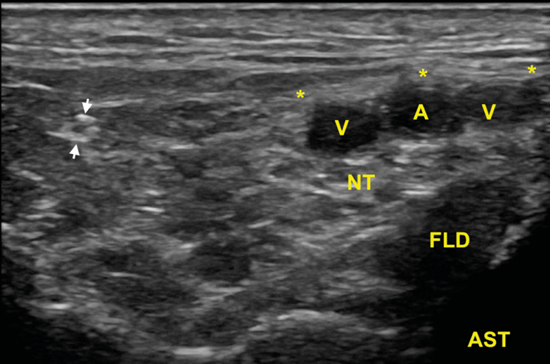

El nervio tibial, que se sitúa en superficie a las estructuras musculotendinosas y bajo la fascia crural, de forma habitual está dispuesto posterior a los vasos tibiales posteriores (Figura 6).

Figura 6. Túnel tibiocalcáneo. El examen en eje corto, bajo la fascia crural (*) y de anterior a posterior, muestra el tendón tibial posterior (TP), el tendón flexor largo de los dedos (FCD) aún con fibras musculares, y el músculo flexor largo del primer dedo (FLD). Entre estas dos estructuras se encuentra el haz neurovascular que está formado por las venas (V), la arteria (A) tibial posterior y por el nervio tibial (rodeado por X).

El nervio tibial tiene forma más o menos redondeada, patrón fibrilar con zonas punteadas anecogénicas e hiperecogénicas que corresponden a los haces nerviosos y al tejido conectivo de sostén, la típica imagen denominada de “sal y pimienta”, y sección transversal entre 10 mm26 y 12,7 mm27 a nivel del maléolo tibial (Figura 7).